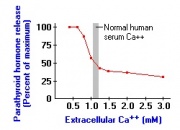

| 17:46, 26 במאי 2013 | הורמוןפ2.jpg (קובץ) |  |

17 קילו־בייטים | Nachi | 1 | |

| 17:46, 26 במאי 2013 | הורמוןפ1.jpg (קובץ) |  |

36 קילו־בייטים | Nachi | 1 | |

| 17:40, 26 במאי 2013 | הורמון2.jpg (קובץ) |  |

22 קילו־בייטים | Nachi | 1 | |

| 17:40, 26 במאי 2013 | הורמון1.jpg (קובץ) |  |

15 קילו־בייטים | Nachi | 1 | |